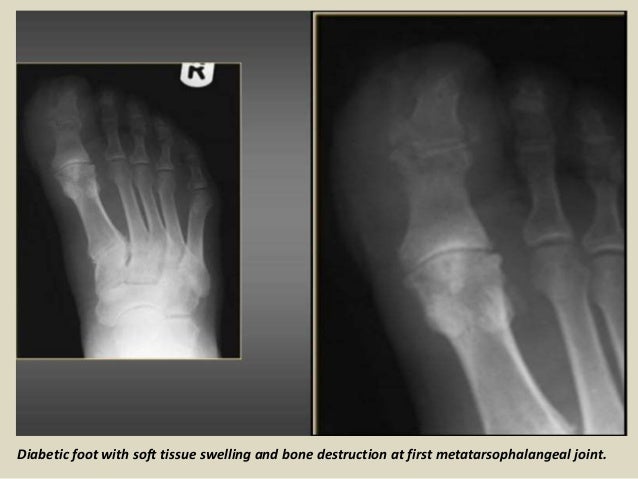

X-ray Early absent or subtle finding. Charcots disease neuropathic arthritis is a rare cause of joint destruction. In the foot the most frequent location for a diabetic Charcots joint subluxation is the tarsometatarsal Lisfrancs joints.

Diabetic cheiroarthropathy also known as diabetic stiff hand syndrome or limited joint mobility syndrome has been reported in 8 to 50 of all patients with type 1 diabetes and is also seen in type 2 diabetic patients. If not caught in its earliest stage the joints in the foot collapse and the foot eventually becomes deformed. Fracture avascular necrosis infection gout 2.